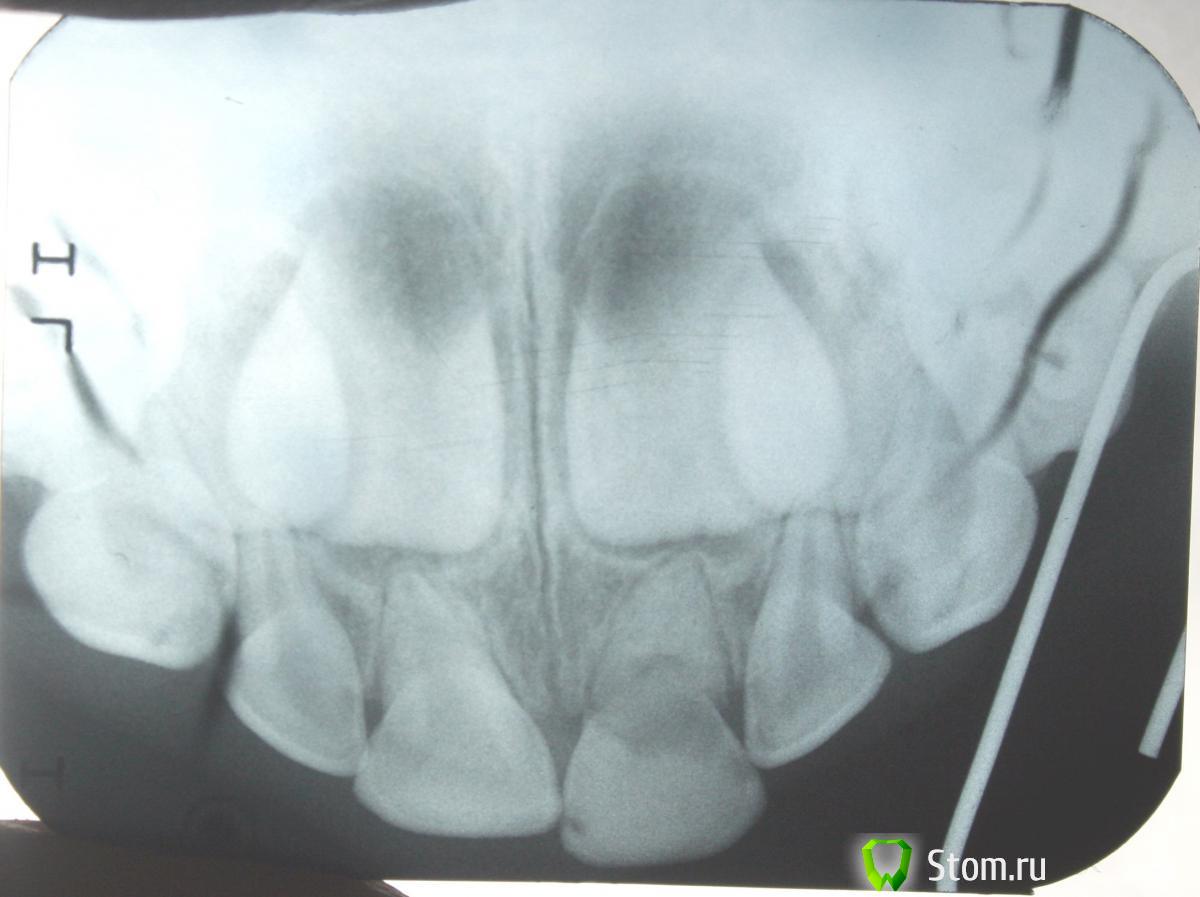

samsonov Опубликовано 24 января, 2012 Поделиться Опубликовано 24 января, 2012 Приветствую всех,детских в особенности.Только что прислали Rg. Мальчику 4, 5 лет. Травма 5.1.Что посоветуете,удалять не хочется...Спасибо (Деткам зубки не шинировал) Ссылка на комментарий

samsonov Опубликовано 24 января, 2012 Автор Поделиться Опубликовано 24 января, 2012 (изменено) Всем спасибо, удалил. Изменено 24 января, 2012 пользователем samsonov Ссылка на комментарий